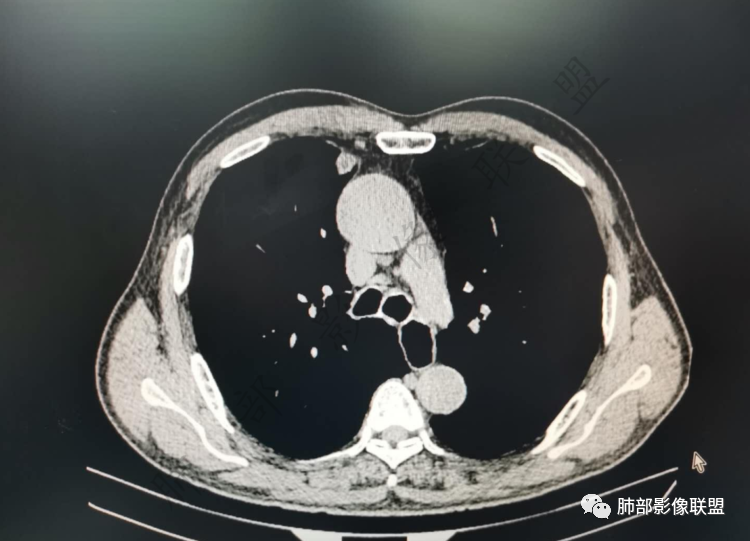

右肺上类圆形叶结节,周边见细软毛刺,增强后呈环形明显强化,内部坏死,邻近胸膜光滑,结合病史2个月明显增大,考虑炎性可能性大。

老年男性,炎性指标略高,肺气肿背景。右肺上叶胸膜下结节,部分边缘平直,部分稍膨隆,供血血管增粗,增强扫描病灶中心密度减低,呈环形强化,邻近脂肪间隙清晰。考虑炎性肉芽肿或慢性炎症,鉴别鳞癌。

老年男性,白细胞计数及CRP稍高,右肺上叶结节,两个月来有增大,部分边缘可见边界模糊的GGO,局部边缘平直、凹陷,临近胸膜增厚,内见坏死,坏死区边界未见明显壁结节,壁较厚而且均匀强化,支气管似乎有扩张然后截断,近端血管增粗明显。考虑炎性病变,脓肿?有结核病人密切接触史,注意是否为结核。有点难以理解的是为什么右侧内乳动脉增粗明显。

老年男性,无症状,炎性指标增高。肺气肿背景,右肺上叶前段结节,边缘部分平直部分澎隆,血管集束,支气管至病变边缘似截断,近端扩张。增强环形强化,中心坏死。两月内病灶增长太快,考虑炎性肉芽肿,慢性脓肿?结核?癌待排。

内乳动脉关系似乎不密切